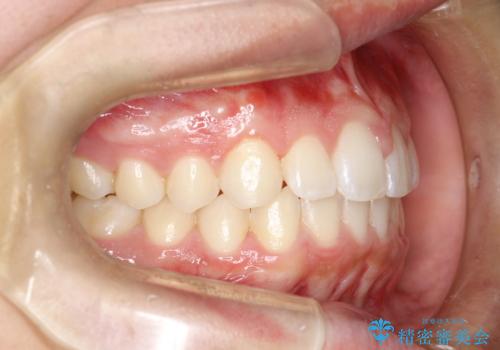

前歯の隙間がきになる インビザラインですきっ歯の治療

- 上の前歯の隙間を主訴に来院されました。

正中に隙間があり、かみ合わせが深い過蓋咬合という状態でした。

インビザラインにて矯正治療を行いました。

しっかり使っていただけたので、スムーズに治療を終了することができました。